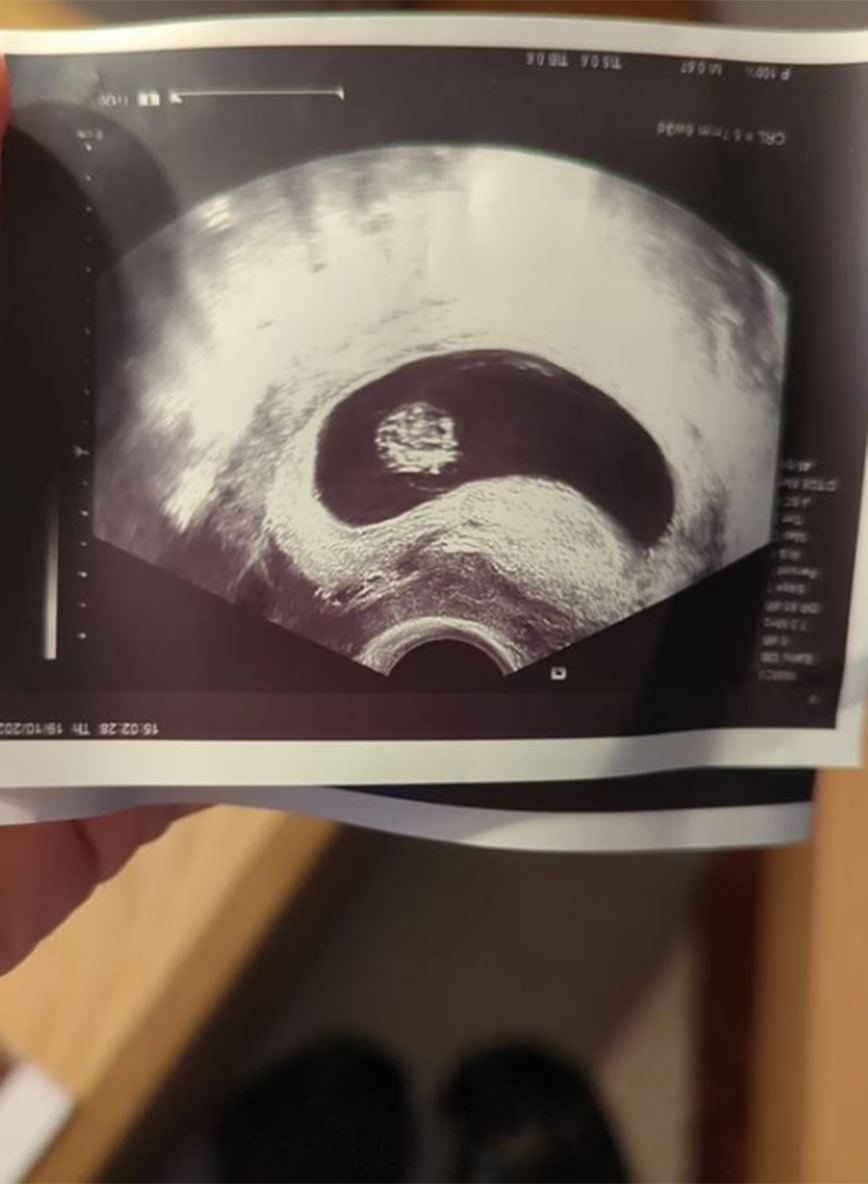

Συγκεκριμένα, έκανε ανάρτηση στο Instagram και δημοσίευσε φωτογραφίες με τη φουσκωμένη της κοιλίτσα, όπως και με τον πρώτο υπέρηχο, ενώ στη λεζάντα έγραψε το εξής:

«Δυο ψυχές, ένα σώμα».

Οι φωτογραφίες που δημοσίευσε η Ντάνη Γιαννακοπούλου: